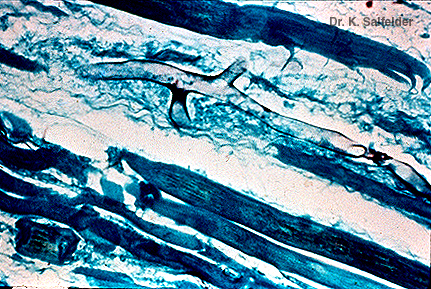

Abb. 15,19: Mukormykose

Die Hyphen faerben sich gut mit dieser speziellen Faerbung an. Grocottmethode